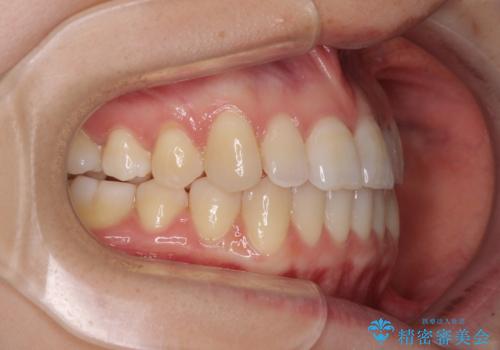

前歯のクロスバイト インビザラインによる矯正治療

- 前歯のクロスバイトを気にして来院された患者様です。

短期間での治療を希望され、ワイヤー装置とインビザラインとで悩んでいましたが、自己管理を徹底すると言うことでインビザラインによる矯正治療を行うこととしました。

しっかりとインビザラインの装着時間を守っていただいたので、1年弱で矯正治療を終えることができました。